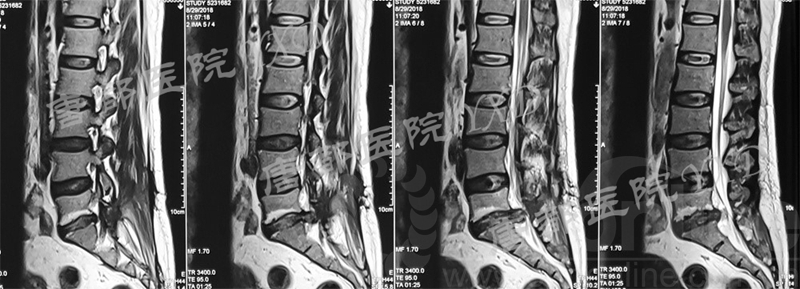

影像学检查:

诊断:腰椎椎间融合术后融合器后移

手术方案:显微镜辅助MI-TLIF腰椎翻修术

术中视频:http://api.orthonline.com.cn/attach/Case3.mp4(术中发现因前次手术全椎板及关节突切除,TLIF的第一步,即关节突关节的定位落脚点难以找到。显微镜下通过Kambin三角解剖位置,进行从外至内的解剖,寻找cage尾端;此外,因大量瘢痕渗血,难以进行充分止血;但在显微镜的照明和放大视野下,操作均可在不伤及神经的前提下进行。由于终板骨质吸收,椎间隙塌陷,导致术野内可同时看到出行根和走行根。而在显微镜下,能够通过调整景深和视线角度,精准充分处理椎间隙骨性终板。无手术并发症)